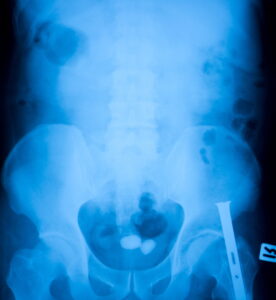

Most people are familiar with kidney stones, but stones can form in all organs along the urinary tract: the kidneys, ureters, urethra, and the bladder. Bladder stones develop when mineral deposits in urine begin to crystallize and form a hard mass. These stones can affect men, women, and children – although men are most likely to develop stones as they age.

Under normal circumstances, urine is regularly expelled from the bladder during urination. However, some conditions may cause the bladder from completely emptying. Urine that remains in the bladder can begin the process of crystallization and the development of bladder stones. Stones inside the bladder can also be caused by the following:

- Foreign materials in the bladder such as kidney stones. While kidney stones are formed from different materials, a kidney stone that becomes lodged in the bladder can continue to grow.